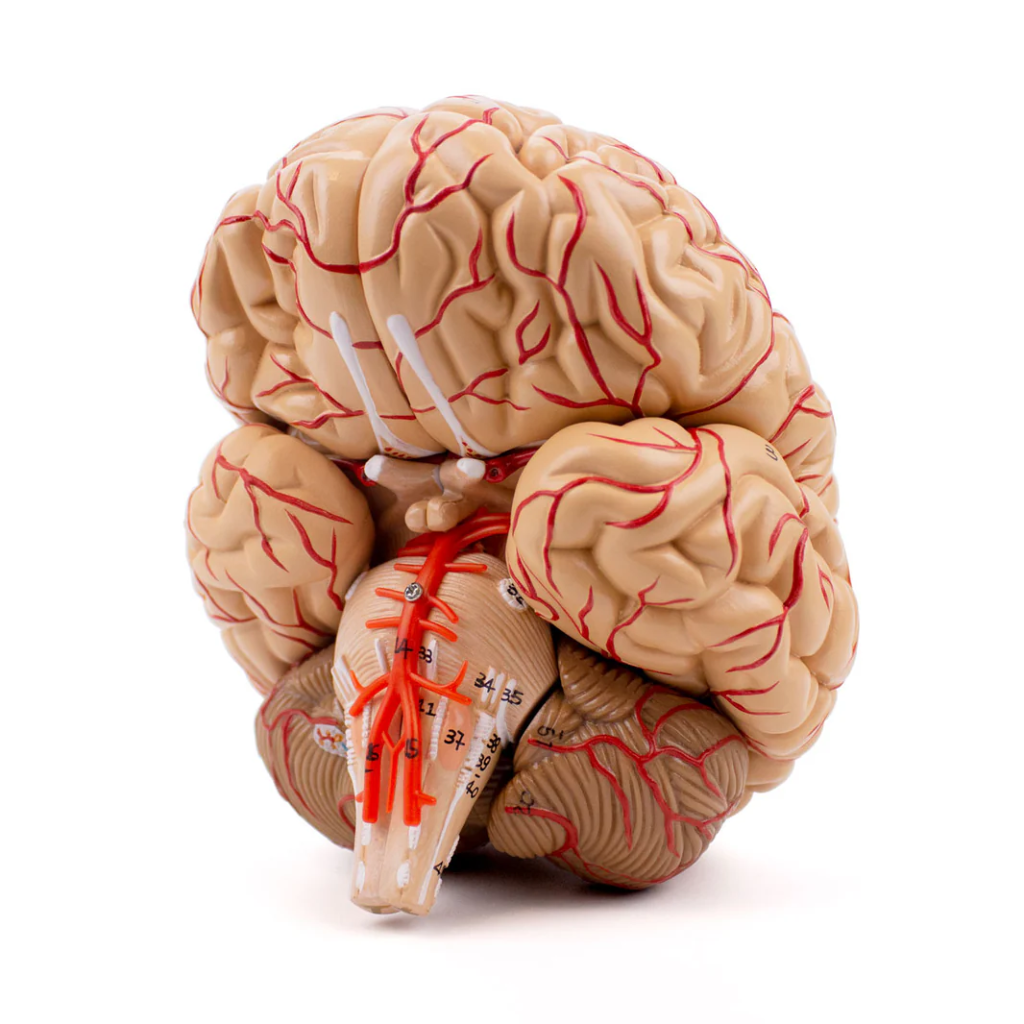

3B Scientific

Encéfalo de lujo con arterias en la base de la cabeza, desmontable en 8 piezas

Precio de venta$22,344.58

3B Scientific

Cerebro de Lujo con Arterias, desmontable en 9 piezas - 3B Smart Anatomy

Precio de venta$18,177.53